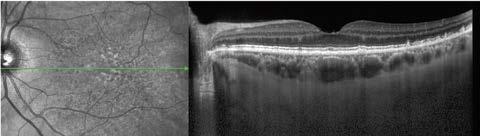

Se realizó abordaje multimodal con tomografía de coherencia óptica macular, angiografía con fluoresceína de campo amplio, autofluorescencia y seguimiento fotográfico, con lo que descartamos un proceso tumoral y se confirma diagnóstico de coriorretinopatía exudativa hemorrágica periférica.

Imagen 4. Estudios multimodales postquirúrgicos.